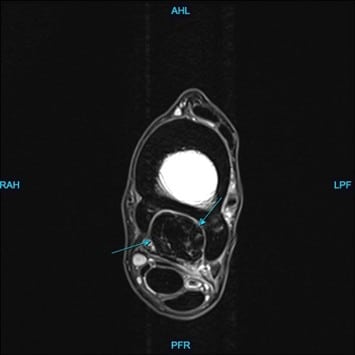

At Animal Imaging, Hugo was placed under general anesthesia and multiplanar MR images were acquired. The gelding was found to have moderate to marked, ill-defined fiber disruption of the origin of the proximal suspensory ligament with marked subchondral and endosteal sclerosis of proximal plantar third metatarsal. The proximal and body of the suspensory ligament was generally enlarged and rounded. The gelding also had marked subchondral sclerosis of dorsal central and third tarsal bones. Numerous, small cortical and subchondral cystic lesions of the dorsal distal intertarsal and tarsometatarsal joints.

Hugo was diagnosed with subchondral bone injury of third metatarsal bone with concurrent marked enthesitis and desmopathy of the origin of the proximal suspensory ligament. The gelding also had moderate to marked chronic desmopathy of the proximal suspensory ligament and body and Moderate to marked distal intertarsal and tarsometatarsal osteoarthropathy.